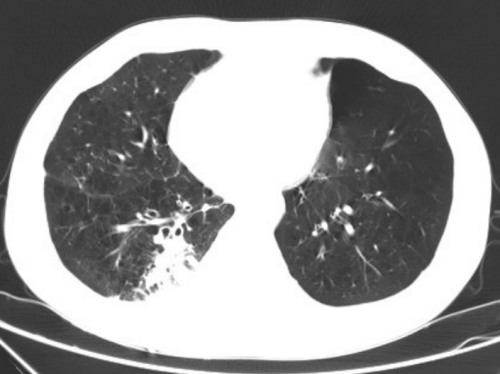

据了解,王先生长期吸烟,有多年的慢性支气管炎、肺气肿,11月24日因CT体检发现右下肺结节,于12月1住进普胸外科、心脏大血管外科。普胸外科、心脏大血管外科副主任医师罗化接诊了他。经过PET-CT检查,王先生患肺癌可能大,无远处及淋巴结转移,需手术治疗。但考虑王先生年龄大,又长期吸烟,有慢性阻塞性肺部疾病,肺功能差,难以耐受肺全麻胸腔镜手术。科室副主任、主任医师杨继承查看患者后立即组织团队研究讨论,决定采取肺部微波消融治疗。为了缓解王先生的紧张情绪,杨继承告知王先生:“目前针对肺结节、肺癌有很多方法,除了常规胸腔镜手术外,还可以进行局部消融术,就是在CT引导下经皮肺插一根针到肺部结节中,几分钟结节就消失,不需要全麻,恢复快,创伤小”。王先生听后打消了疑虑,欣然接受。

12月4日,杨继承带领手术团队在CT引导下给王先生进行了肺部结节微波消融手术。选取合适体位、CT确认进针方向后,首先局麻下进行结节穿刺活检,快速病理确认为肺鳞癌,确定为患者微波消融。杨继承考虑结节离胸膜近,消融过程中微波针热刺激胸膜会造成患者疼痛,于是给予患者人工气胸,使肺结节远离壁层胸膜,然后在CT引导下插入15cm长的微波消融针进入肺部结节进行消融。5分钟后结节消失,手术顺利,患者未感不适,于12月7日顺利出院。

术后三天结节部位坏死、炎性水肿改变